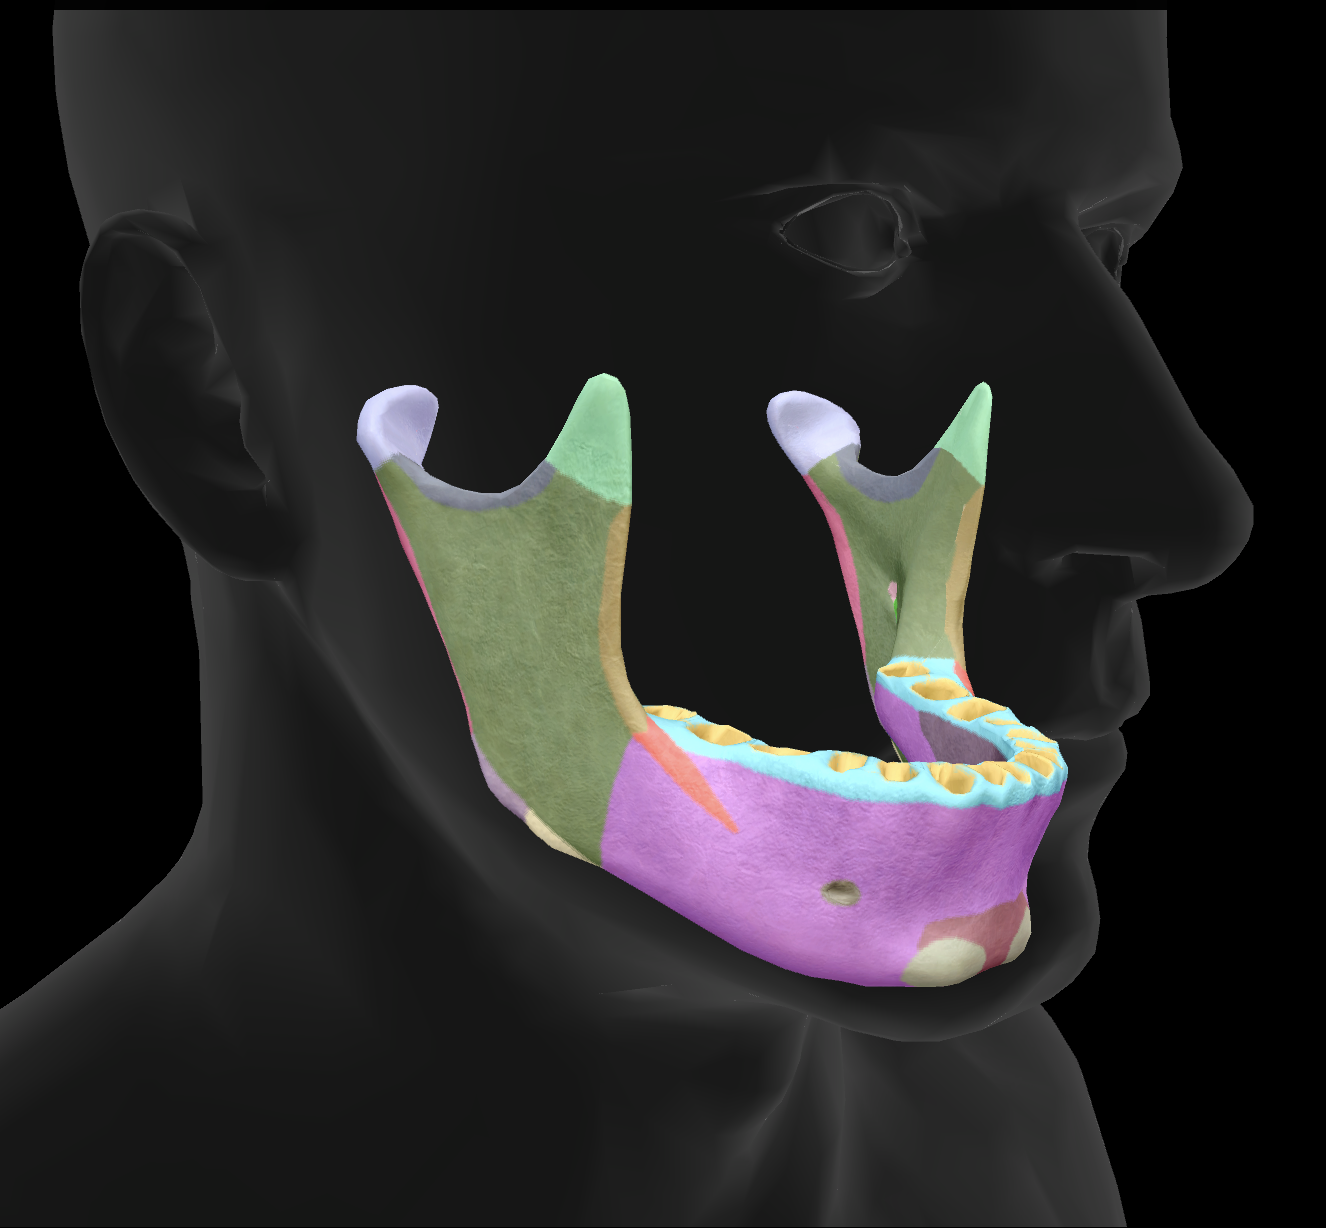

What is the name of this feature?

mandibular condyles

What is the name of this feature?

ramus

What is the name of this feature?

alveolar process

What is the name of this feature?

mandibular notch

What is the name of this feature?

angle

What is the name of this feature?

body

What is the name of this feature?

coronoid process